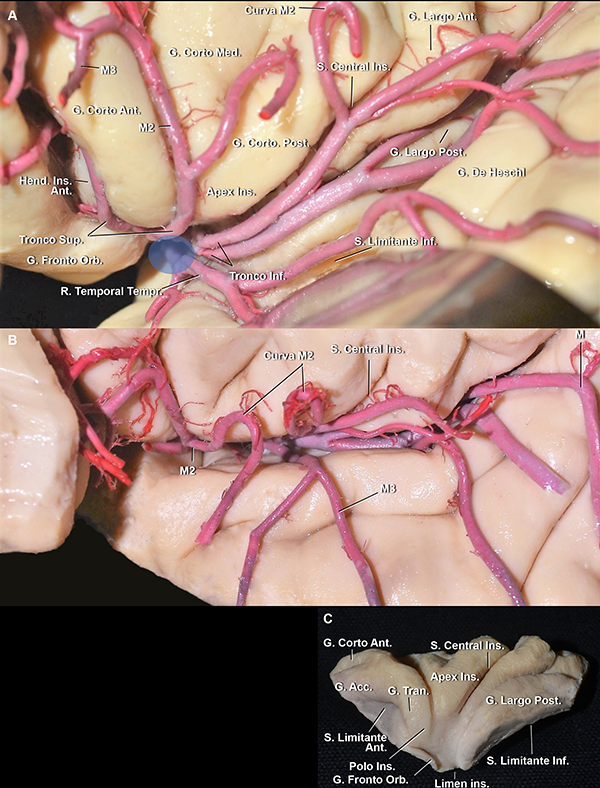

El compartimiento opercular anterior se define como el espacio entre los giros orbitarios posterior y lateral y el plano polar del lóbulo temporal (Figura 5A y 6B). Por otro lado, la hendidura insular anterior se localiza entre la ínsula y los giros orbitarios lateral y posterior (Figura 1C,6B,7A).

El compartimiento esfenoidal presenta una disposición de inferomedial a superolateral. El extremo medial del compartimiento está delimitado por la membrana aracnoidea silviana proximal, que lo separa de la cisterna carotídea y es perforada por el segmento proximal de M1 de la ACM (Figura 8B). La membrana aracnoidea silviana proximal está adherida a la estría olfatoria lateral y a la incisura rinal, o también llamada incisura temporal (Figura 1B y 8B). El segmento anterior del uncus se ubica medial a la membrana silviana proximal. El techo del compartimiento esfenoidal está compuesto por la sustancia perforada anterior (SPA) y los giros fronto-orbitarios. El núcleo caudado y lentiforme, así como también el brazo anterior de la cápsula interna, se localizan por encima del techo de este compartimiento. La pared posterior del compartimiento esfenoidal es el área donde la SPA se fusiona con el lóbulo temporal. El limen insular es su límite lateral (Figura 1A y B). El receso del limen, que es el área comprendida entre la arteria lentículo estriada más lateral y el limen insular, fue hallado en todos los hemisferios estudiados en este trabajo y midió un promedio de 12 mm de largo (Figura 1A). Este receso es un espacio desprovisto de arterias perforantes. El piso del compartimiento esfenoidal es el plano polar. Este compartimiento contiene principalmente: la mitad distal del segmento M1, las arterias perforantes de la SPA, las ramas corticales tempranas de la ACM, los troncos arteriales post bifurcación que pudieran nacer de este segmento si la bifurcación de la ACM fuera proximal al limen insular, la parte distal de la arteria recurrente de Heubner y la vena cerebral media profunda (Figura 1B y D).

Distalmente al limen insular, en la profundidad de los ramos superficiales, presentando una orientación diagonal, se localiza la parte cisternal lateral de la FS. Este segmento es también conocido como compartimiento operculoinsular lateral. Este compartimiento se encuentra compuesto por tres espacios estrechos: 1) el compartimiento opercular lateral, entre el opérculo frontoparietal y temporal, en un nivel intermedio, 2) la hendidura insular lateral y 3) la región retroinsular (Figura 6). Los últimos dos espacios se encuentran en el nivel más profundo de la cisterna silviana. La hendidura insular lateral se localiza entre la ínsula y los opérculos, extendiéndose desde el limen insular hasta el punto en el que los surcos limitantes insulares superior e inferior se conectan, punto conocido como punto insular posterior. Dicha hendidura tiene un bolsillo superior e inferior. La región retroinsular se extiende desde el punto insular posterior hasta el extremo distal de la FS. Esta región se relaciona superficialmente con el giro supramarginal, superiormente, y los giros temporales transversos, inferiormente (Figura 6B).

Figura 7:A. vista lateral del lóbulo insular izquierdo del mismo espécimen que en la figura 1D y 9D. La superficie lateral de la ínsula está totalmente cubierta por M2 y sus ramas. El limen insular (círculo sombreado azul) limita la parte basal de la lateral de la FS y el segmento M1 de M2. Las arterias corticales tempranas no tienen un segmento insular dado que nacen del segmento M1 y pasan directamente al M3. B. Vista superior del mismo espécimen. El opérculo frontoparietal fue removido. C. Vista inferior de la ínsula del mismo espécimen. Los giros cortos tienen una dirección hacia el ápex insular. Debajo del ápex, la proyección inferior de los giros cortos se dirige hacia el polo insular. Los giros posteriores largos empiezan en el plano polar como un giro único que luego se divide en dos. S: surco; G: giro; Ant: anterior; post: posterior; Ins: insular; Acc: accesorio; Tran: transverso; Inf: inferior; Sup: superior; Orb: orbital; Hend: hendidura; Tempr: temprana.

Figura 9: A. Vista latero superior, quirúrgica, de una FS izquierda (mismo espécimen que en Figura 1B y C). Cabeza de flecha azul: limen insular. El limen insular se encuentra medial y anterior a la punta de la pars triangularis. A su vez, el polo insular se encuentra superolateral al limen insular y el ápex insular, superolateral al polo. Cuanto más posterior en la cisterna silviana, más profundo es el compartimiento opercular. Posterior al giro de Heschl, el opérculo temporal tiene una dirección recta en el plano axial, haciendo más dificultosa la apertura de la FS. B. Vista aumentada de A. C. Vista anterolateral de un hemisferio derecho. El opérculo frontoparietal fue removido. La bifurcación de la ACM se localiza proximal al limen insular (cabezas de flecha azul). D. Vista superolateral del mismo espécimen que en Figura 1D y 7. Las ramas corticales tempranas de la ACM pasan por el limen insular, así como los troncos postbifurcación. Ins: insular; G: giro; Bifur: bifurcación; S: surco; Orb: orbitalis; Fronto Orb: frontoorbitario; R: ramo; Tempr: temprano; Op: opercularis; Tri: triangularis; Pl: plano; Lim: limitante; inf: inferior.

La ACM se divide en 4 segmentos: M1 (esfenoidal), M2 (insular), M3 (opercular) y M4 (cortical).

El segmento M1 se origina en la cisterna carotídea y se relaciona superiormente con la SPA e inferiormente con el segmento anterior del uncus (Figura 1D). Este segmento perfora la membrana silviana proximal y entrando al compartimiento esfenoidal de la cisterna silviana. En este segmento, se identificaron el origen tanto de las arterias lenticuloestriadas como de las ramas corticales tempranas (Figura 1C y D). En nuestra serie, 9 de los 10 hemisferios presentaron por lo menos una rama cortical temprana.

El segmento M2 comienza en el punto en donde el segmento M1 cambia de dirección. Este punto se conoce como la rodilla o genu de la ACM y se localiza en el limen insular (Figura 9). El segmento M1 tiene una orientación mediolateral, perpendicular al punto de vista del neurocirujano; el segmento M2, una orientación inferosuperior, paralela al punto de vista del neurocirujano (Figura 10C). Durante la cirugía, una manera de diferenciar el segmento M1 de M2 es observando su dirección. El 80% de las bifurcaciones de la ACM se localizaron en o proximal al limen insular.

Figura 11: A. Vista anteroposterior de una angiografía carotídea derecha. El uncus (cabeza de flecha violeta) se relaciona anteriormente con el segmento proximal de M1. El ápex uncal apunta hacia la bifurcación carotídea. Inmediatamente distal al genu de la ACM se ubica la pars triangularis (cabeza de flecha roja grande). Las pequeñas cabezas de flecha naranjas indican el segmento M2 de la ACM y, consecuentemente, la corteza insular. El punto M se define como el punto donde el ramo más posterior de M2 cambia de sentido alejándose de la ínsula hacia el opérculo, en relación estrecha con el extremo posteromedial del giro de Heschl. La ínsula se proyecta desde el genu de la ACM hasta el punto M. Las ramas de M3 sobre el plano temporal tienen un curso recto (flechas verdes). B. Vista lateral de la misma angiografía. Se identifica el triángulo silviano. Su borde anterior (cabeza de flecha amarillo) y superior (cabezas de flecha azul) lo marcan los loops de M2. Su borde inferior lo indica el tronco inferior de M2 cursando por el surco limitante inferior insular (cabeza de flecha verde). Los troncos postbifurcación se ramifican cerca del polo insular y el ápex (círculo celeste). C y D. Vistas coronales de una RMN. El plano polar tiene una dirección oblicua inferior (barra roja) (C) y el plano temporal una dirección recta (barra amarilla) (D). P Ins Ant: punto insular anterior.

El primer compartimiento silviano que es disecado desde el punto silviano anterior es el compartimiento opercular anterior. La mayoría de las FS tienen un compartimiento opercular anterior curvilíneo irregular. Esto se debe frecuentemente a una pars orbitalis prominente que indenta y comprime al plano temporal. Una vez que este compartimiento es disecado, si el cirujano continúa proximalmente y en profundidad por la fisura, se accede al compartimiento esfenoidal. Con una cánula de aspiración delicada con mínima presión de succión, pinzas bipolares bayonetada y microtijeras, se progresa la disección.

Las ramas y segmentos de la ACM no siempre se identifican con claridad. En función de poder hacerlo, es útil disecar los vasos arteriales desde distal a proximal hasta que la bifurcación carotídea es identificada, y luego seguir a la ACM en dirección opuesta, de proximal a distal. M1 debe ser disecada por su cara anterior. Esto es porque las arterias lenticuloestriadas usualmente nacen de su cara superior o posterosuperior (Figura 1C,10C, 10D).

Si la superficie lateral de la FS necesita ser abierta, la disección continua distalmente. La técnica microquirúrgica es la misma que la descripta. El limen insular y la bifurcación de la ACM sirven como un punto de referencia confiable para comenzar a disecar al lóbulo insular, de anterior a posterior. El limen insular es un área donde se pueden encontrar muchos vasos arteriales. No solo los troncos superior e inferior de M2 se localizan aquí, sino también, las ramas corticales tempranas tienen su curso. Los opérculos son separados utilizando presión suave con la pinza bipolar y la cánula de aspiración delicada, siempre con la ayuda de algodones pequeños y, también, de microtijeras. A medida que los opérculos son disecados, se puede introducir algodones para gradualmente abrir el compartimiento operculoinsular lateral sin gran presión, hasta que toda la extensión de la fisura es disecada.

La parte opercular del giro temporal superior está dividida en dos: anteriormente, el plano polar o planum polare, y posteriormente, el plano temporal o planum temporale. La estructura neural que marca esta división es el giro transverso anterior o, simplemente, giro de Heschl. Este es el giro más voluminoso del opérculo temporal, tiene una orientación diagonal y su extremo posteromedial apunto hacia el brazo posterior de la cápsula interna, el núcleo pulvinar del tálamo y el atrio (Figura 12A, B, D).15,22

El plano polar es un área integrada por giros cortos oblicuos menores: los giros de Schwalbe (Figura 6B).25 Por un lado, tiene una orientación lateromedial en el eje axial, escondiendo su punta anterior debajo del giro orbitario posterior (Figura 6).15 Por otro lado, tiene una orientación oblicua inferior en el eje coronal, que contribuye al agrandamiento del espacio subaracnoideo en el punto silviano anterior.22,23

El plano temporal está compuesto por dos o tres giros transversos. Es un área de forma triangular cuyo ápex apunta hacia el atrio ventricular. El giro de Heschl y la parte posterior del giro temporal superior constituyen el área auditiva primaria (Figura 6A, 10A y B).22 En su extremo anterolateral, el giro de Heschl se encuentra en el mismo plano coronal que el giro postcentral. Además, se evidenció que el giro de Heschl a su vez se encuentra en el mismo plano que el conducto auditivo externo (CAE) (Figura 5). En el plano coronal, tiene una orientación horizontal, haciendo que la disección de la fisura en esta área sea más dificultosa.

El limen insular es un área anatómica arqueada, medial al polo insular, que yace sobre al fascículo uncinado y se extiende desde el punto en el que el giro largo insular posterior se encuentra con el polo temporal, hasta los giros frontoorbitarios (Figura 13A). El fascículo uncinado (FU), junto con el fascículo fronto-occipital inferior (FFOI) componen la parte ventral de la cápsula externa. El FFOI está constituido por fibras que conectan a los giros frontales medio e inferior con el lóbulo occipital. Las fibras del FFOI comienzan en el lóbulo frontal, en un plano profundo al FA, pasa profundo al punto insular anterior, posterior al FU y luego, cursando a través del giro temporal superior y medio, alcanza la parte posterior de los lóbulos parietal y occipital. El FU conecta estructuras temporales y frontales paralímbicas: el polo temporal con las áreas orbitofrontales y septal (Figura 13).24

Tanriover et al.26 observa que entre la arteria lenticuloestriada más lateral y el limen insular hay un espacio de 15mm promedio desprovisto de arterias perforantes. Esta área es nombrada como receso del limen. En nuestros hemisferios, fue de 12 mm promedio.

La superficie lateral de la ínsula está dividida por el surco central de la ínsula en una parte anterior y otra posterior. La parte anterior representa dos tercios de la superficie lateral de la ínsula (Figura 4C y 6B). El surco central de la ínsula está orientado en paralelo al surco central y es el área insular más densamente vascularizada (Figura 7A).27 El extremo inferior del surco central insular apunta al limen. Los giros cortos anterior, medio y posterior se encuentran en la parte anterior de la ínsula, aunque se han descripto tanto como cinco giros cortos (Figura 6B).6,26

El ápex insular es el área más lateral, superficial y prominente de la ínsula, y es el punto de encuentro de los giros cortos insulares (Figura 7A, 12A, 12C). Está localizado superolateralmente al polo insular. La continuación basal de los giros cortos insulares está dirigida hacia la parte superior del polo insular (Figura 7C).

Posterior al surco central insular, los giros largos anterior y posterior son encontrados. Los giros largos se originan como un giro único cerca del limen insular, que luego se divide por un surco largo posterior (Figura 12B).

Anatomía vascular y su correlación angiográfica

Existe un consenso a lo largo de la literatura de que la bifurcación silviana se localiza más frecuentemente en el limen insular. Según Rhoton,12 Gibo3 y Wen,15 86-90% de las bifurcaciones se localizan proximal al o en el limen insular. Sin embargo, Türe,27 reporta en su serie que 57.5% de las ACM se bifurcan en el limen, 15% 5 a 8 mm proximal al, y 27.5% 4 a 10 mm distal al limen insular. Finalmente, Yasargil17 considera que en el 50% de los casos, M1 se divide en el limen insular. En nuestra serie, en el 50% de los casos la bifurcación de la ACM se localizó proximal al, 30% en, y 20% distal al limen insular. Así también, la presencia de ramas corticales tempranas en el 90% de nuestros especímenes, se correlaciona con el 91% publicado por Tanriover et al.26 Definimos a las ramas corticales tempranas, como aquellas arterias nacidas en M1 que no tienen relación estrecha con la corteza insular e irrigan áreas corticales temporales o frontales.

Se dice que la angiografía digital (AD) muestra el esqueleto en el cual las estructuras neurales son organizadas. Su comprensión profunda es esencial para el planeamiento quirúrgico. La corteza insular está cubierta e irrigada por el segmento M2 (Figura 7A). Consecuentemente, en una AD, el lóbulo insular se localiza inmediatamente medial a M2 (Figura 11A y B).21 Los límites anterior, superior e inferior del lóbulo insular también pueden ser reconocidos en la AD. Los puntos de cambio de dirección, o loops, de la ACM distal al genu marcan la transición M2/M3 y se localizan en el surco limitante insular anterior y superior (Figura 7A y B). El tronco inferior de M2 cursa a lo largo del surco limitante inferior (Figura 7A). El punto donde el ramo más posterior de M2 cambia de dirección y se aleja de la ínsula dirigiéndose hacia el opérculo temporal (transición M2/M3) es el punto M o silviano, en la AD (Figura 12B, 11A, 11B).12,14,15,26,30 El punto M es un reparo imagenológico de gran utilidad. Este punto indica el extremo posterior insular y la parte más posteromedial del giro de Heschl. Así también, en una incidencia anteroposterior, el punto M indica la posición de, de lateral a medial, el brazo posterior de la cápsula interna, el pulvinar del tálamo y el atrio (Figura 12B).

El triángulo silviano6,14,15 es un reparo encontrado en la incidencia lateral estricta en un AD. Sus bordes son dibujados por los loops M2 anterior y superiormente, y por el tronco inferior cursando por el surco limitante inferior insular, inferiormente. Este triángulo tiene un ángulo superoanterior recto, marcando el punto insular anterior. El contenido de este triángulo es el lóbulo insular y el core central. Inmediatamente por fuera del triángulo se encuentran los ventrículos laterales (Figura 11B).

La bifurcación carotídea se relaciona con el ápex uncal y el segmento proximal de M1 se relaciona inferiormente con el segmento anterior del uncus. Más aún, el genu de M1 se localiza en el limen insular, por lo tanto, en una AD, marca el borde anterior de la ínsula. La pars triangularis está ubicada unos milímetros distales al genu de M1. Dado que el giro precentral cubre el tercio medio de la ínsula, se puede inferir que el giro precentral en una AD se localiza en el punto medio del triángulo silviano. Finalmente, el extremo posterior del lóbulo insular se localiza en el punto M. Consecuentemente, lesiones vascularizadas localizadas en el genu de M1, son encontradas unos pocos milímetros proximales a la pars triangularis, cerca del polo insular; lesiones localizadas inmediatamente distal al genu, se relacionan superficialmente con la punta de la pars triangularis; y aquellas posicionadas en el punto medio entre el genu y el punto M, son mediales al giro precentral (Figura 11A y B).15

Las ramas M3 que cursan sobre el plano polar son más curvilíneas que aquellas del plano temporal, a causa de la superficie relativamente más plana de la primera. El primer segmento recto de M3 identifica el extremo lateral del giro de Heschl (Figura 11A).15 Entonces, el giro de Heschl está enmarcado entre el punto M y el primer tramo recto de M3 (Figura 7B).